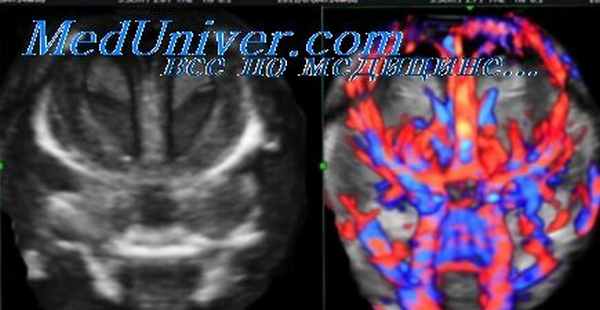

Внутричерепная гипотензия: КТ-исследования и их интерпретация